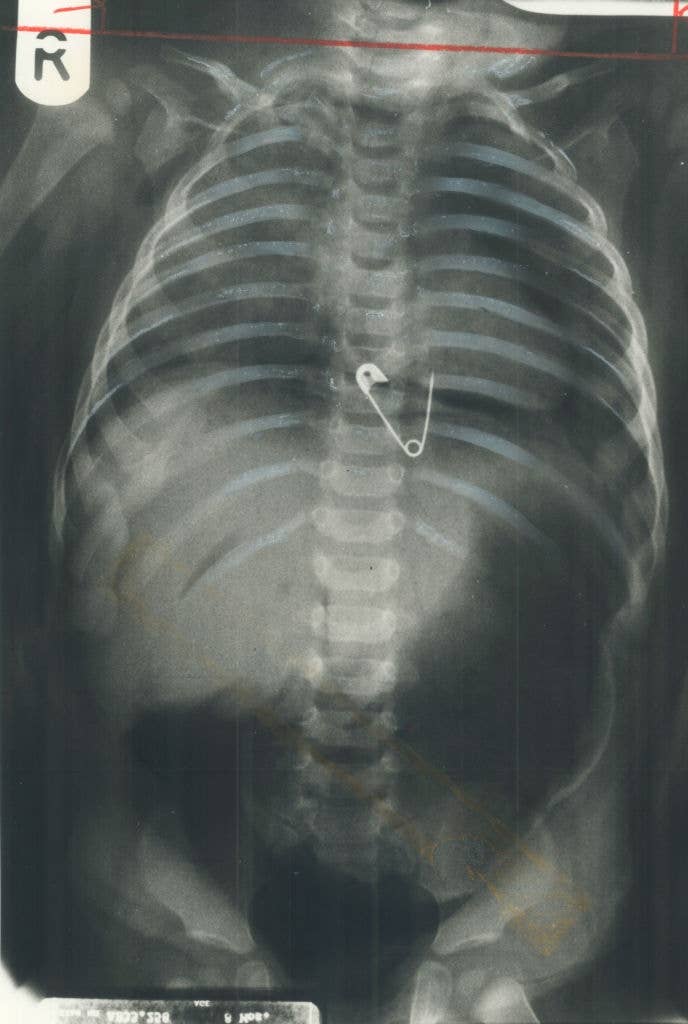

Surgeons, What's The Most Jaw-Dropping Thing You've Seen In The OR?